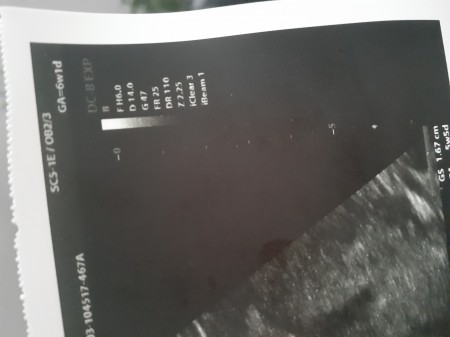

6 Haftalik Gebelik Ve Hamilelik Goruntusu Facebook Hamilelik